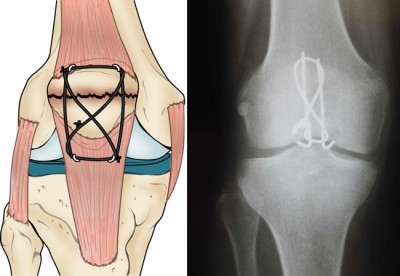

5.Compression fixation of the aticular surface combinde with a tensionband

tension band using K-wires #3 using a wire driver , two double-ended #3 K-wire are placed at the fracture site

with Figure of eight tension band wire can be used